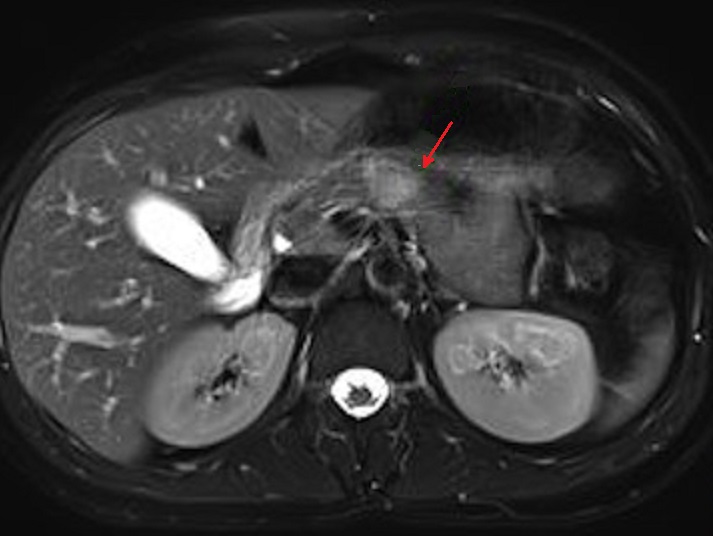

L'IRM : C'est technique

avait une sensibilite resemble la TDM . Aspect radiologique

IRM d'une tumeur endocrine du pancreas est image hypointense

sur T1 ( relative avec parenchyme du pancreas ) et

hyperintense sur les coupes pondere T2 . Sur les coupes T1

avec Gadolinium intraveineuse ( Gd ) le tumeur est

hypervascularise et hypersignal .

Meme cas en coupe IRM

ponderation T1 apres injection de Gadolinium

IRM plus C+(Gd) . La tumeur hypervacularisee devient

hyperdense a la phase aterielle , les tumeurs de

forme fibreuse avait le temps de rehaussement

plus tardive |

Un autre cas de tumeur endocrine du corps

pancreas . Aspect radiologique est un nodule

hyperdense a ponderation T2 . Image radiologique IRM

de ponderation T2 en coupe axiale . |